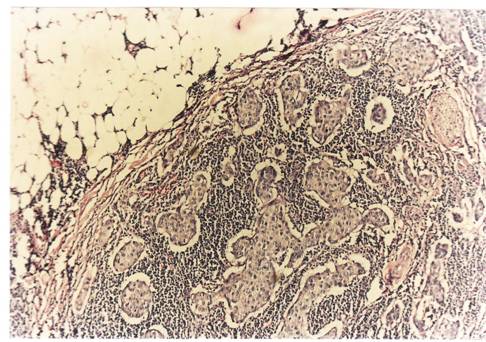

Criterii microscopice de diagnosticare a cancerului mamar

Pentru examenul histopatologic piesele de mamectomie sunt prelucrate prin imparafinare si colorate cu Hematoxilina-Eozina sau, pentru observarea mai buna a tesutului conjunctiv, cu Van Gieson.

Pe preparate colorate, la microscopul optic se observa urmatoarele imagini :